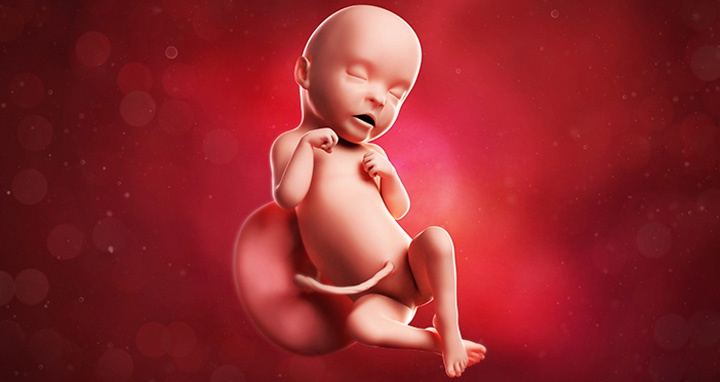

Как выглядит ребенок на 31 неделе беременности

На 31 неделе ваш малыш, скорее всего, занял окончательное положение в утробе. Если он будет рожден головкой вперед, ягодицы сейчас направлены вверх. Внешний вид малыша стал более симпатичным: кожа уплотнилась, и кровеносные сосуды уже не просвечивают. Увеличивается количество подкожного жира, придающего округлые очертания. Ногти достигают кончиков пальцев.

На этом этапе черты лица становятся более четкими, нос и ушки формируются, шея удлиняется. Кожа малыша менее красная и сморщенная, под ней откладывается белая жировая ткань, придающая более натуральный цвет и способствующая разглаживанию кожи. Зрачки начинают реагировать на свет: во время бодрствования глаза открыты, во сне — закрыты. Цвет глаз у всех малышей голубой, а после рождения радужная оболочка накапливает пигменты, меняя цвет на серый, карий или зеленый.

Малыш продолжает накапливать подкожный жир, становясь пухленьким и симпатичным. Это поможет поддерживать температуру тела после рождения.